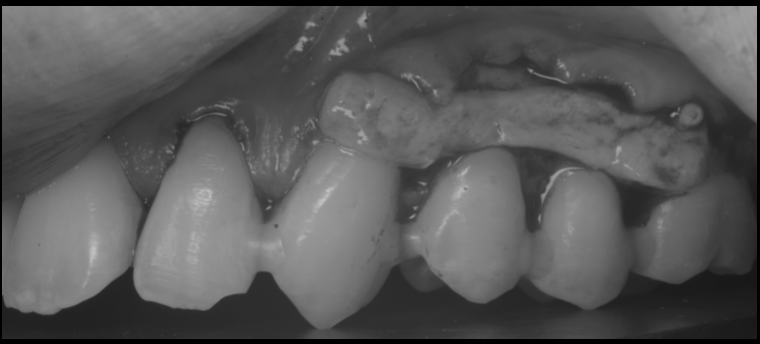

治療中

治療後

治療で得られるメリット:歯周組織の改善、根面う蝕の予防

| 治療内容 | ルートカバー(結合組織移植術) |